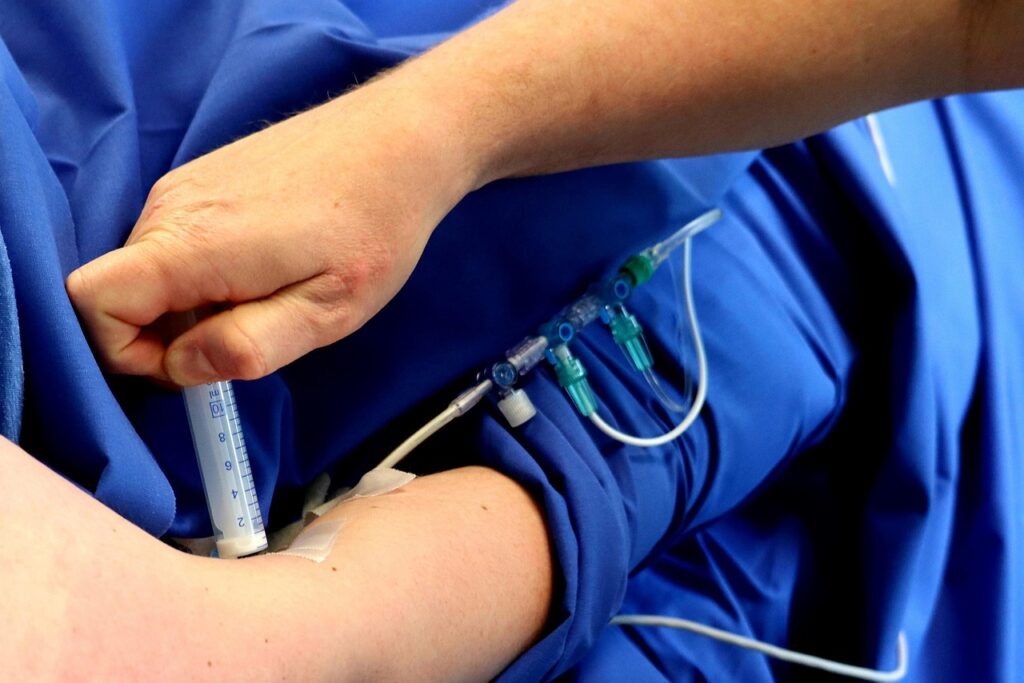

Implante de cateter: quando é indicado e como funciona o procedimento

O implante de cateter é um procedimento amplamente utilizado na prática médica para garantir um…